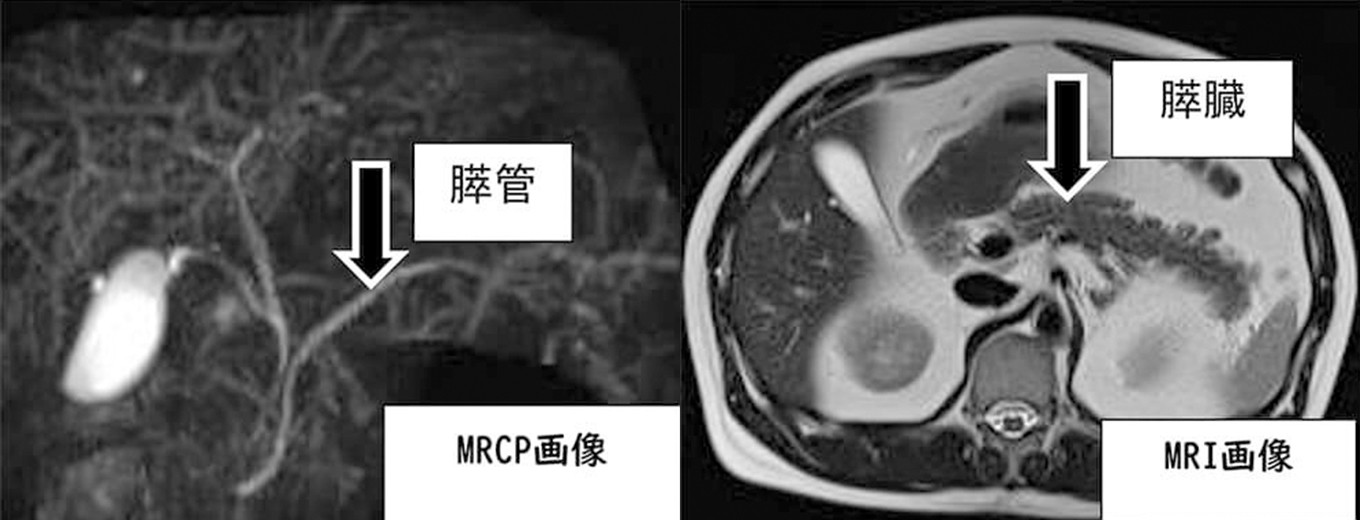

◆膵臓MR検査(MRCP:磁気共鳴胆道膵臓管造影、MRI:磁気共鳴画像)

強力な磁場と電波を用いて体内の水素原子の情報を収集し、それをもとに画像化する検査です。MRCPは膵管(膵液の通り道)や胆のう・胆管(胆汁の通り道)の評価を目的とする検査です。一方、MRIは膵臓自体を断層画像として描出します。